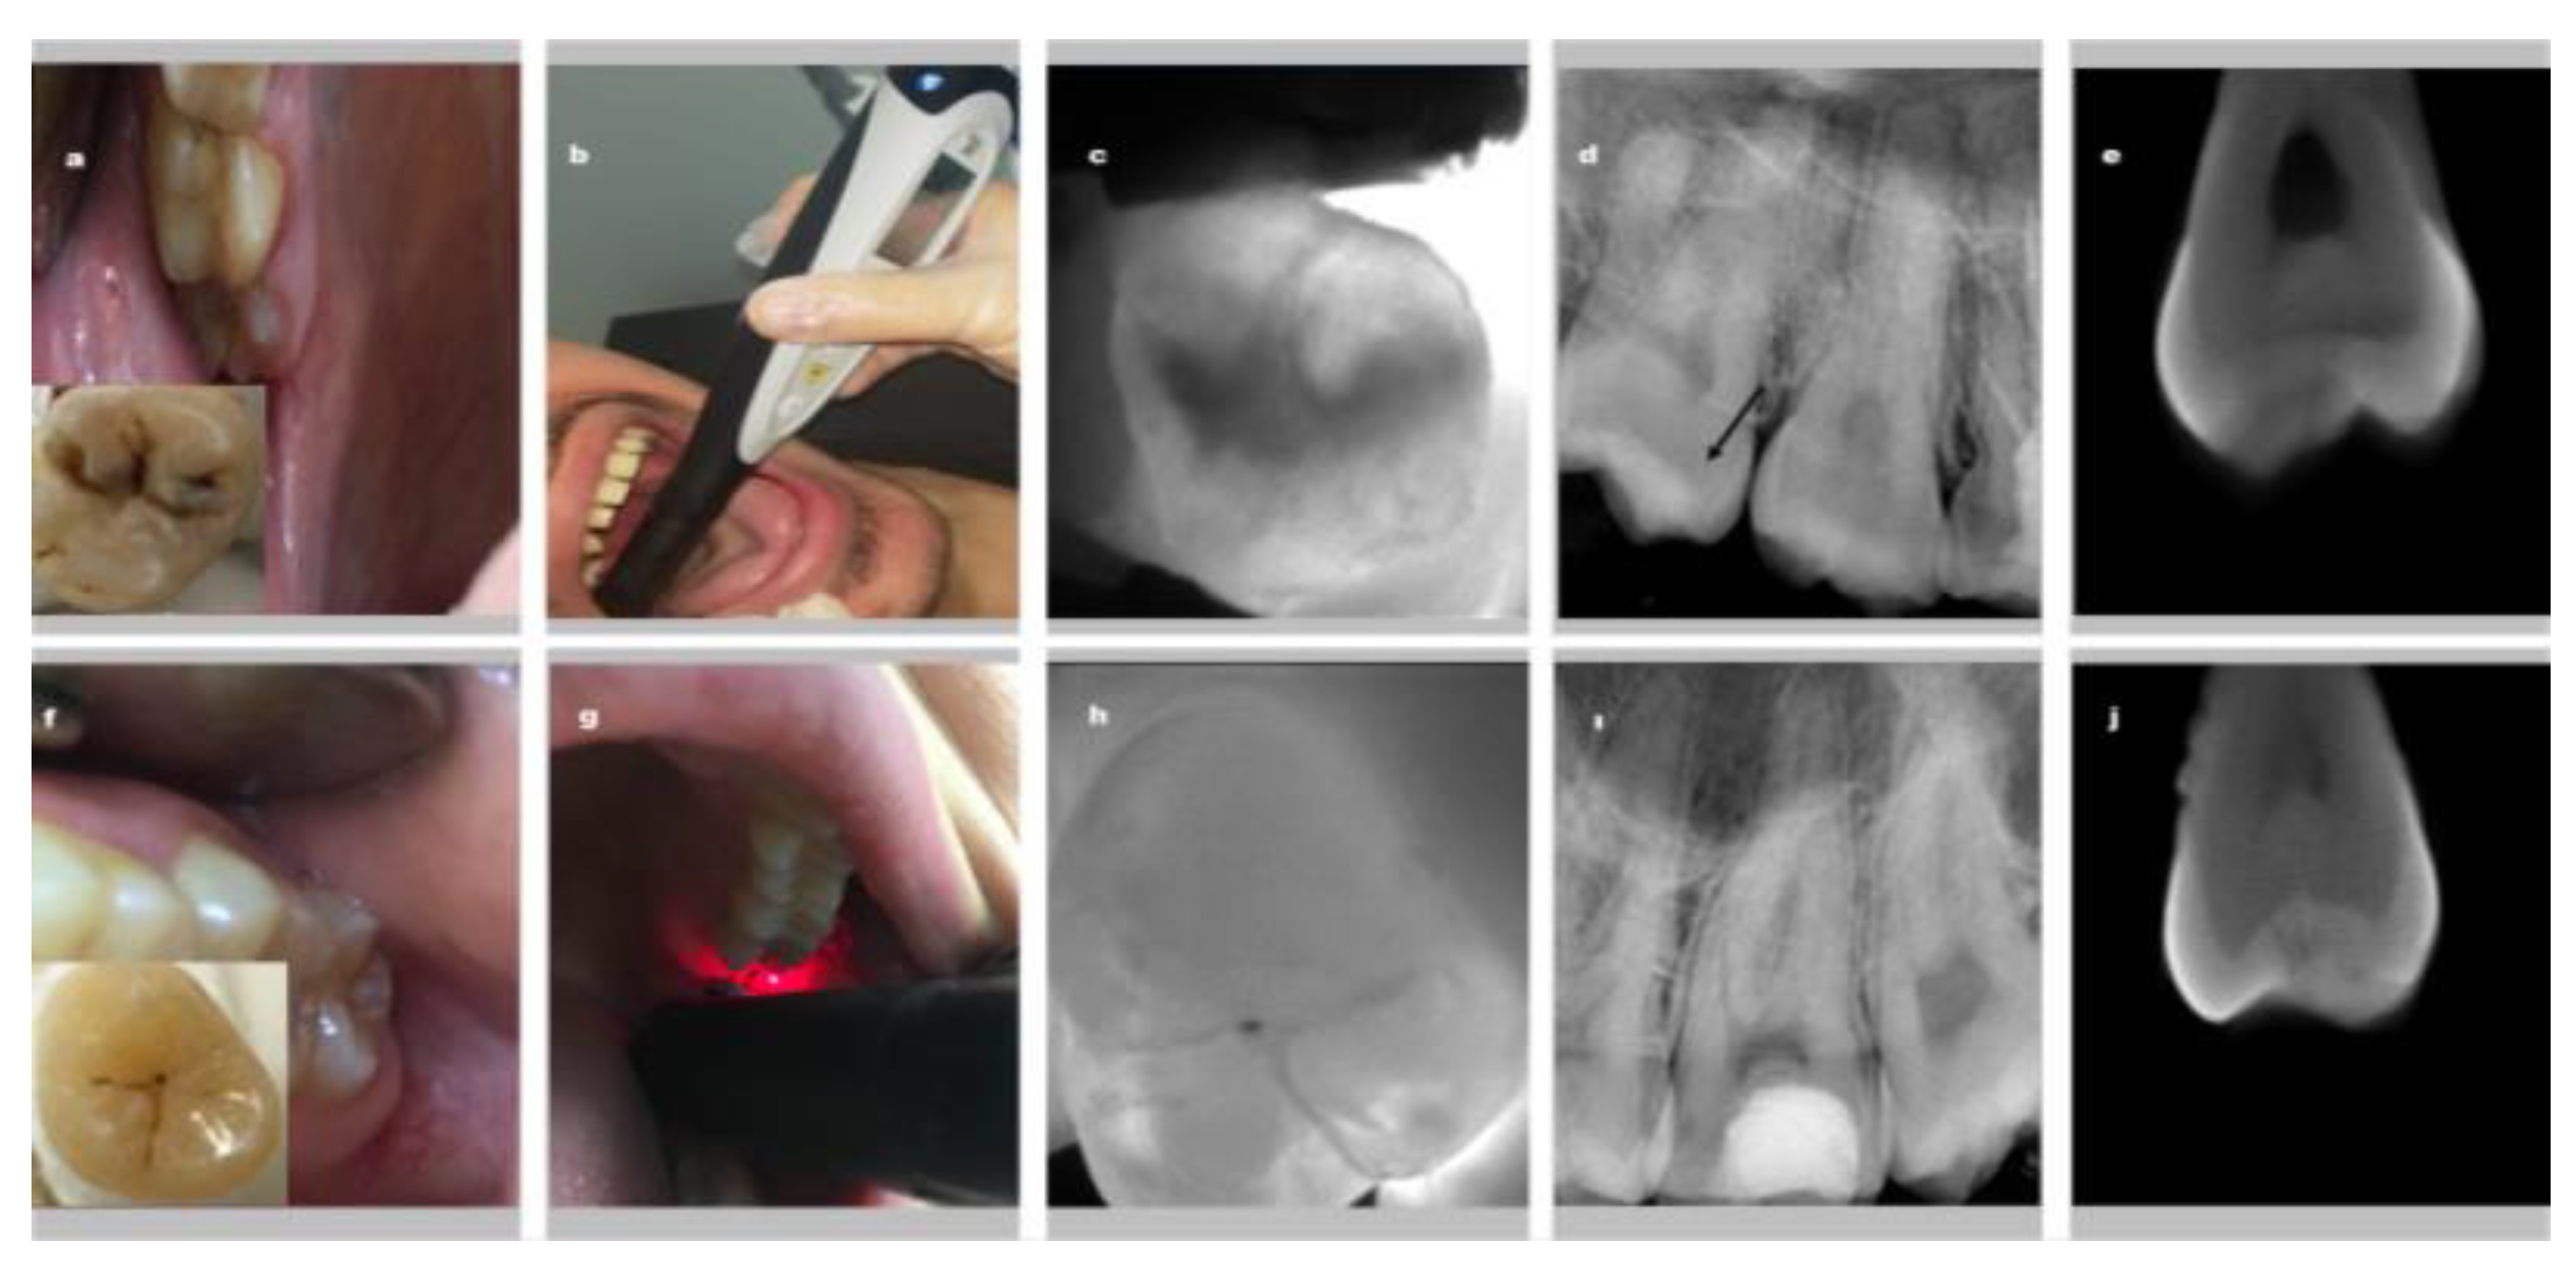

After 1-week interval time, 45 patients were recalled in order to calculate the intra- and inter-observer reliability of each diagnostic method. These patients also consisted of patients who came to their appointments for other dental treatments. Evaluation of all examination methods was repeated independently. Figure 2 shows representative images obtained by using all examination methods for dentin and enamel.

Figure 2.

Representative images demonstrating all examination methods for dentin (a–f) and enamel (f–j) caries; (a–f) clinical visual examination, (b–g) laser fluorescence (c–h) near infrared light transillumination, (d–i) periapical radiography (the black arrow shows dentin caries in figure d), (e–j) micro-CT.